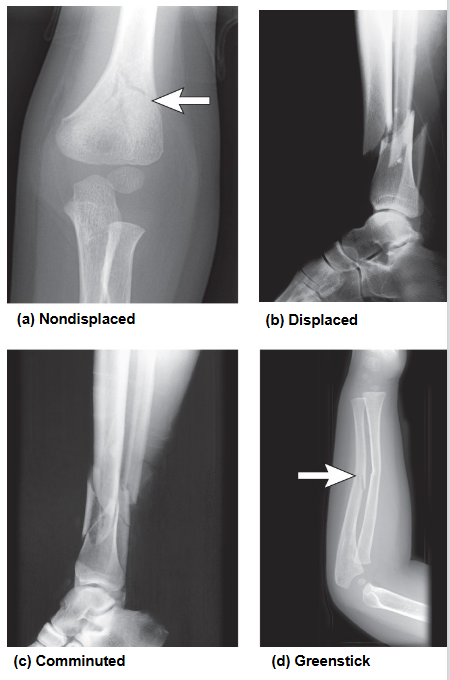

Comminuted fracture

Bone breaks into 3 or more pieces

Greenstick fracture

Incomplete break; one side bends, the other breaks